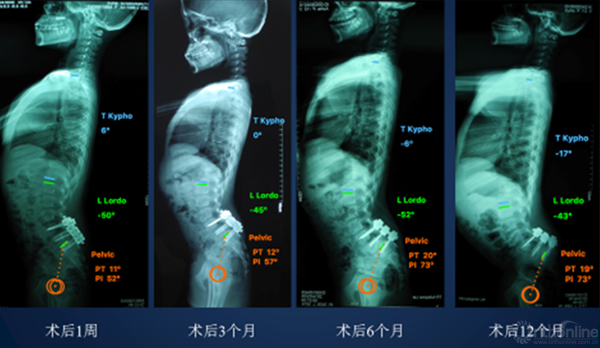

• 矫正腰骶后凸

• 减少假关节

• 恢复矢状面平衡

• 降低邻椎退变

② 我们的病例